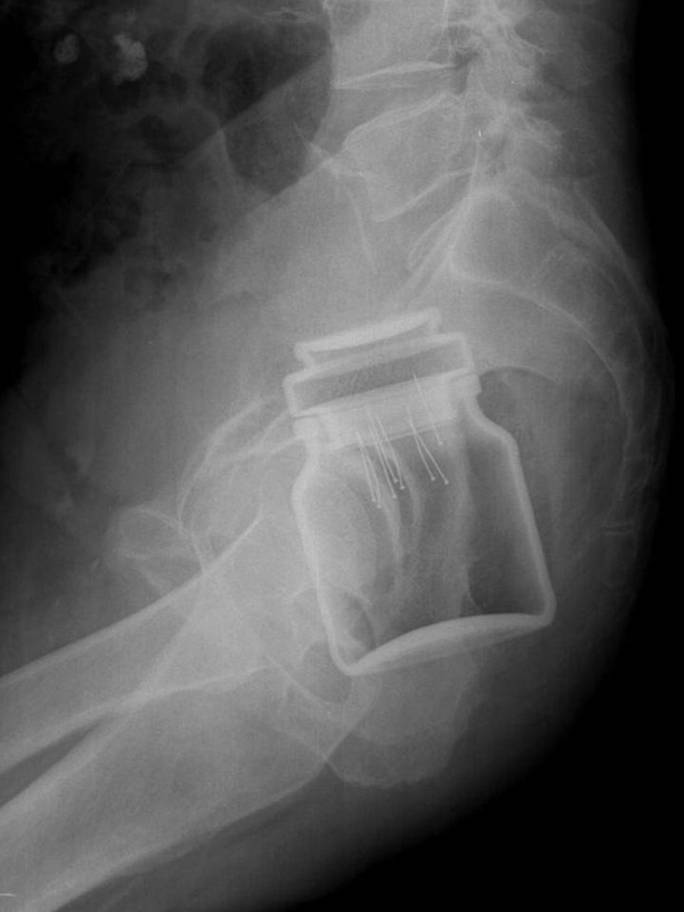

Humans are truly strange creatures and incredibly bizarre things can happen to us. These x-rays will shock even those who think they've seen it all.

X-ray it is one of the best inventions of mankind and in some situations it is indispensable. Especially because it often happens that people, especially children, they swallow objects that are not part of their daily diet. Not to mention the dogs who try to chew everything in sight and thus often end up swallowing inappropriate things.

Radiologists are already quite accustomed to seeing on X-rays strange things and some of these that we have collected for you in the gallery did not surprise them at all. Here is 15+ hacked and sometimes shocking x-rays.